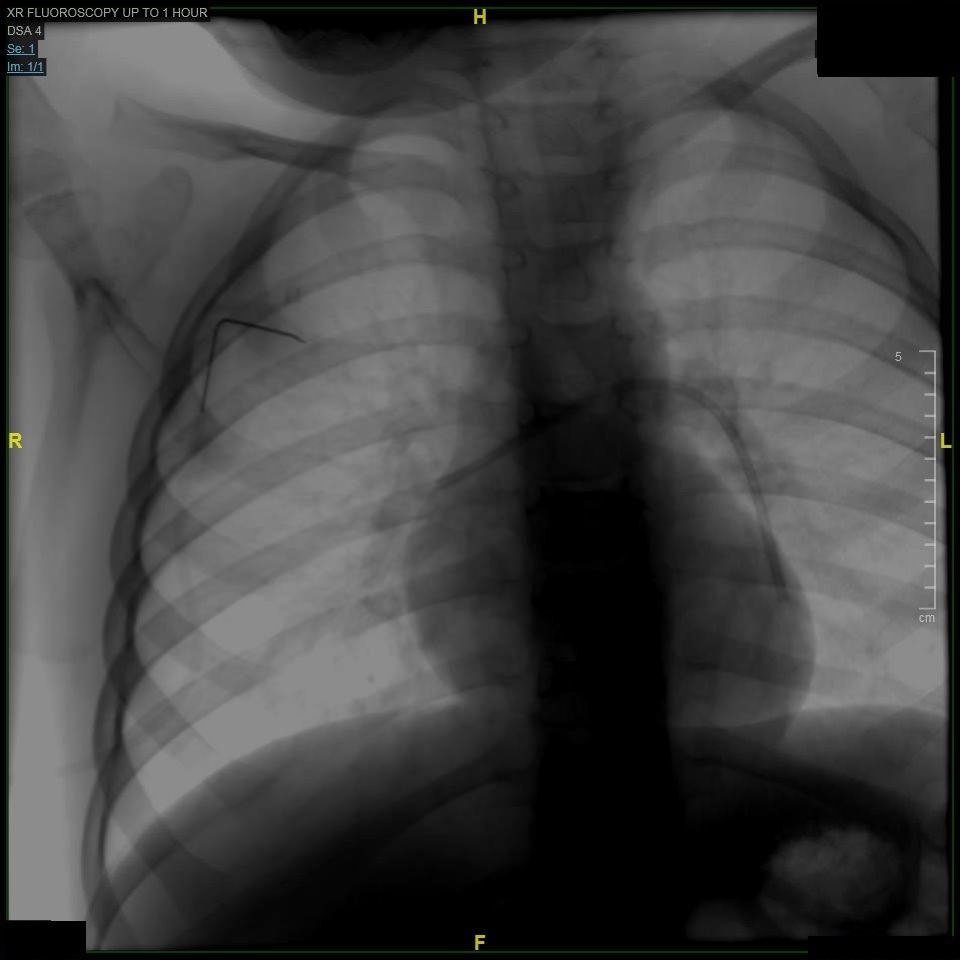

An 11-year-old girl presented to the clinic with concern for worsening vision and daily headaches for the past 6 months, which were located diffusely and mildly relieved with ibuprofen.

10/03/2018